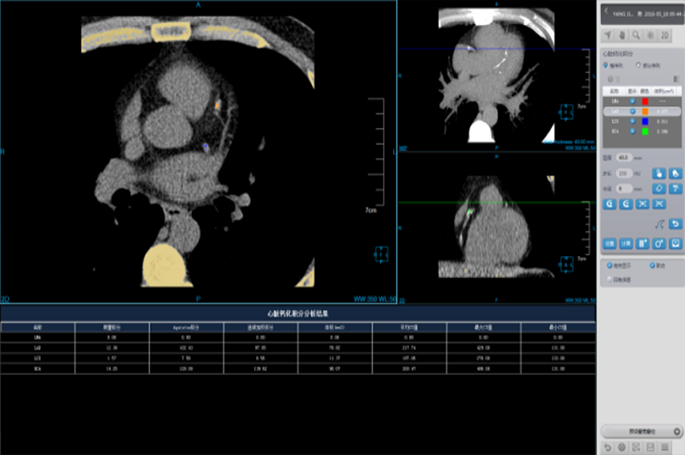

Coronary Calcium Scoring

Estimate the amount of calcium in the coronary arteries

• Agatston score

• Volume score

• ROI information calculation